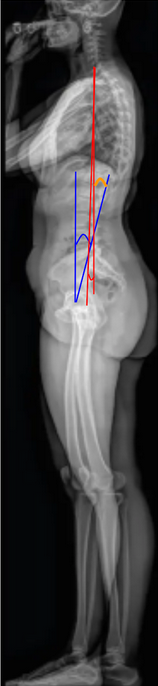

Global Tilt (C7 vertical tilt + pelvic tilt)

Global Tilt (C7 vertical tilt + pelvic tilt) is a comprehensive radiographic parameter that quantifies overall sagittal spinal alignment by combining spinal inclination (C7 vertical tilt) and pelvic retroversion (Pelvic Tilt).

It reflects the angular relationship between the upper spine and pelvis in maintaining upright posture, accounting for both thoracic inclination and pelvic compensation.

Global Tilt = C7 Vertical Tilt + Pelvic Tilt

• Measure C7 Vertical Tilt (C7VT):

• Draw a line from the center of C7 to the center of the femoral heads.

• Measure the angle between this line and the vertical (gravity) reference line.

• Measure Pelvic Tilt (PT):

• Draw a line from the center of the femoral heads to the center of the S1 endplate.

• Measure the angle between this line and the vertical reference line.

• Calculate Global Tilt = C7VT + PT.

• A larger Global Tilt reflects increased anterior spinal inclination and compensatory pelvic retroversion, indicating positive sagittal malalignment.